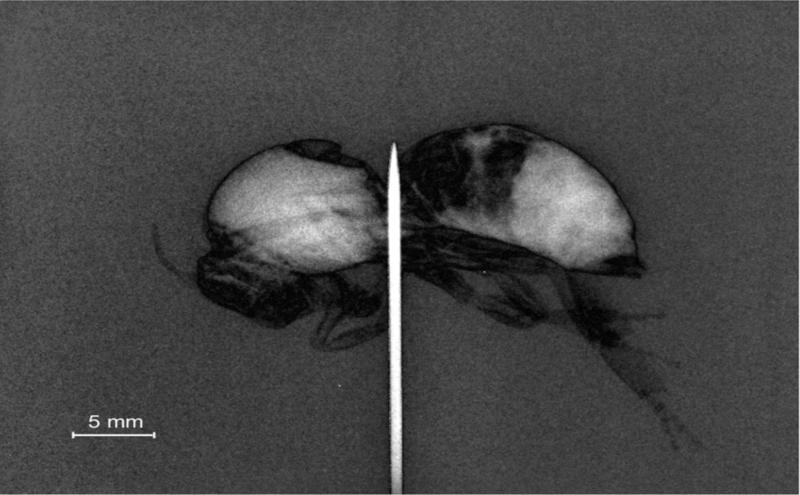

“A vantaxe desta nova tecnoloxía é que, ao ter un foco xerador de raios X de dimensión micrométrica, conséguense imaxes de mellor calidade cunha menor cantidade de raios X”, asegura o catedrático de Física Atómica, Molecular e Nuclear José Benlliure. “Ademais, pódese aplicar unha nova técnica de reconstrución da imaxe, radiografía por contraste de fase, que permite visualizar materiais de diferente densidade, en particular tecidos biolóxicos”. Os investigadores do IGFAE puideron aplicar esta nova técnica tanto en radiografía convencional como a imaxes tomográficas en tres dimensións.

Imaxe radiografía (bidimensional) por contraste de fase dunha abella obtida coa fonte láser de raios X do L2A2 na que se aprecia a capacidade de identificar texidos con diferente densidade Imagen tomográfica (tridimensional) dun conector eléctrico na que se aprecia a capacidade de visualizar a parte interna do conector ao ter unha densidade diferente á capa externa